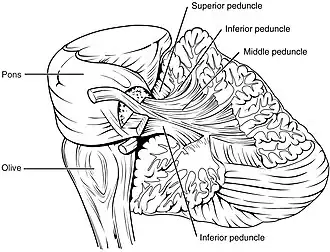

Arbor vitae and cerebellar peduncles.

Arbor vitae and cerebellar peduncles.